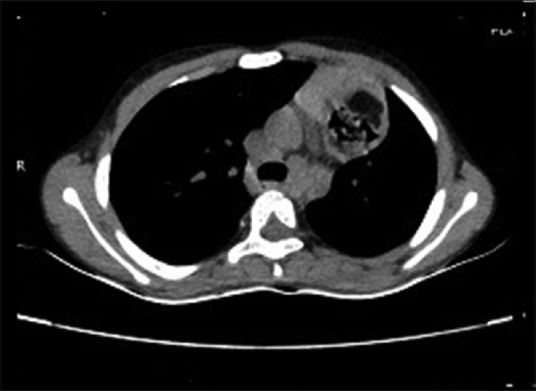

Her investigation yielded hemoglobin was 4 gm% with normocytic normochromic type of anemia, an erythrocyte sedimentation rate of 20 mm at end of 1t hour. Her total leukocyte count and differential leukocyte count were within normal limits, while her tuberculin test was negative. Chest radiograph was suggestive of well-circumscribed mass on upper left side with infective changes [Figure 1]. High-resolution computed tomography (CT) thorax revealed infective changes in both lung fields with well-circumscribed mass of size 4 cm × 4 cm × 4 cm on the left main bronchus and extending on lingual lobe suggestive of thymolipoma [Figure 2]. CT-guided fine-needle aspiration cytology shows fat cells. Intraoperatively, there was a mass of size 4 cm × 4 cm × 4 cm in the anterior mediastinum and communicating with left main bronchus and lingual lobe with cheesy puttaceous material coming out of it and adhere to aorta, pericardium, and pleura. Mass was excised, and partial lobectomy was done. Histopathologically, on cut surface, mass was solid grayish white in color with many cysts of size 1 cm × 1 cm × 1 cm filled with brownish friable material and yellowish fatty area. On microscopy, elements of all three germ layer namely epidermis, skin adnexal structure, adipose tissues in sheets and groups, mature cartilage, muscle tissues, and respiratory epithelium suggestive of mature teratoma were seen [Figures [Figures33 and and44].

| Figure 2:Computed tomography thorax shows well-circumscribed mass in mediastinum